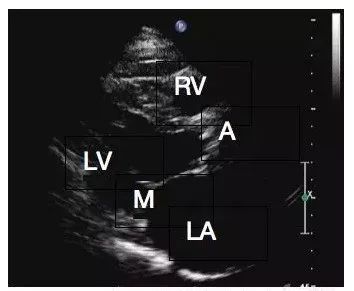

正常左室长轴切面

LV:左室;RV:右室;LA:左房;M:二尖瓣;A:主动脉瓣

正常左室长轴切面

LV:左室;RV:右室;LA:左房;M:二尖瓣;A:主动脉瓣